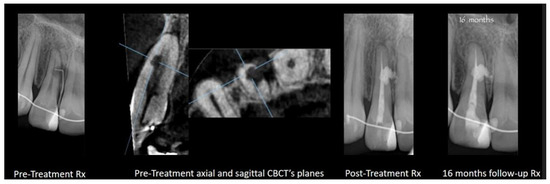

2.6. Iatrogenic Aberrations